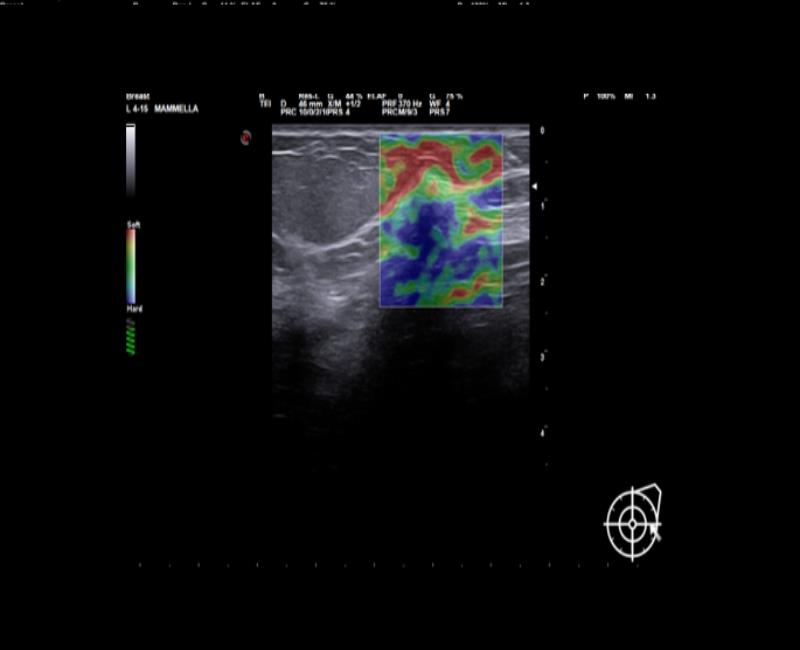

ElaXto – Siêu âm đàn hồi mô định tính xác định độ đàn hồi mô cùng tỷ lệ độ cứng, tỷ lệ đường kính E/B ứng dụng trong vú, giáp, cơ xương khớp và được hướng dẫn bởi hiệp hội siêu âm thế giới WFUMB.